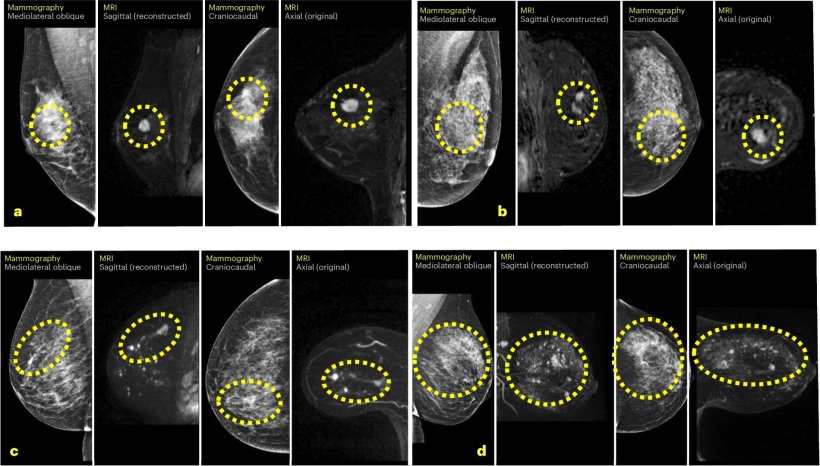

Image source: Salim M, Liu Y, Sorkhei M et al., Nature Medicine 2024 (CC BY 4.0)

The AI tool analysed data of 1,211 women to whom it had assigned high risk scores to mammography exams performed at Karolinska. Principal investigator Fredrik Strand, MD, PhD, advised that the cancer detection rate of participants who had a supplemental MRI was 64.4 cancerous lesions per 1,000 exams, according to a report of interim data published in Nature Medicine.